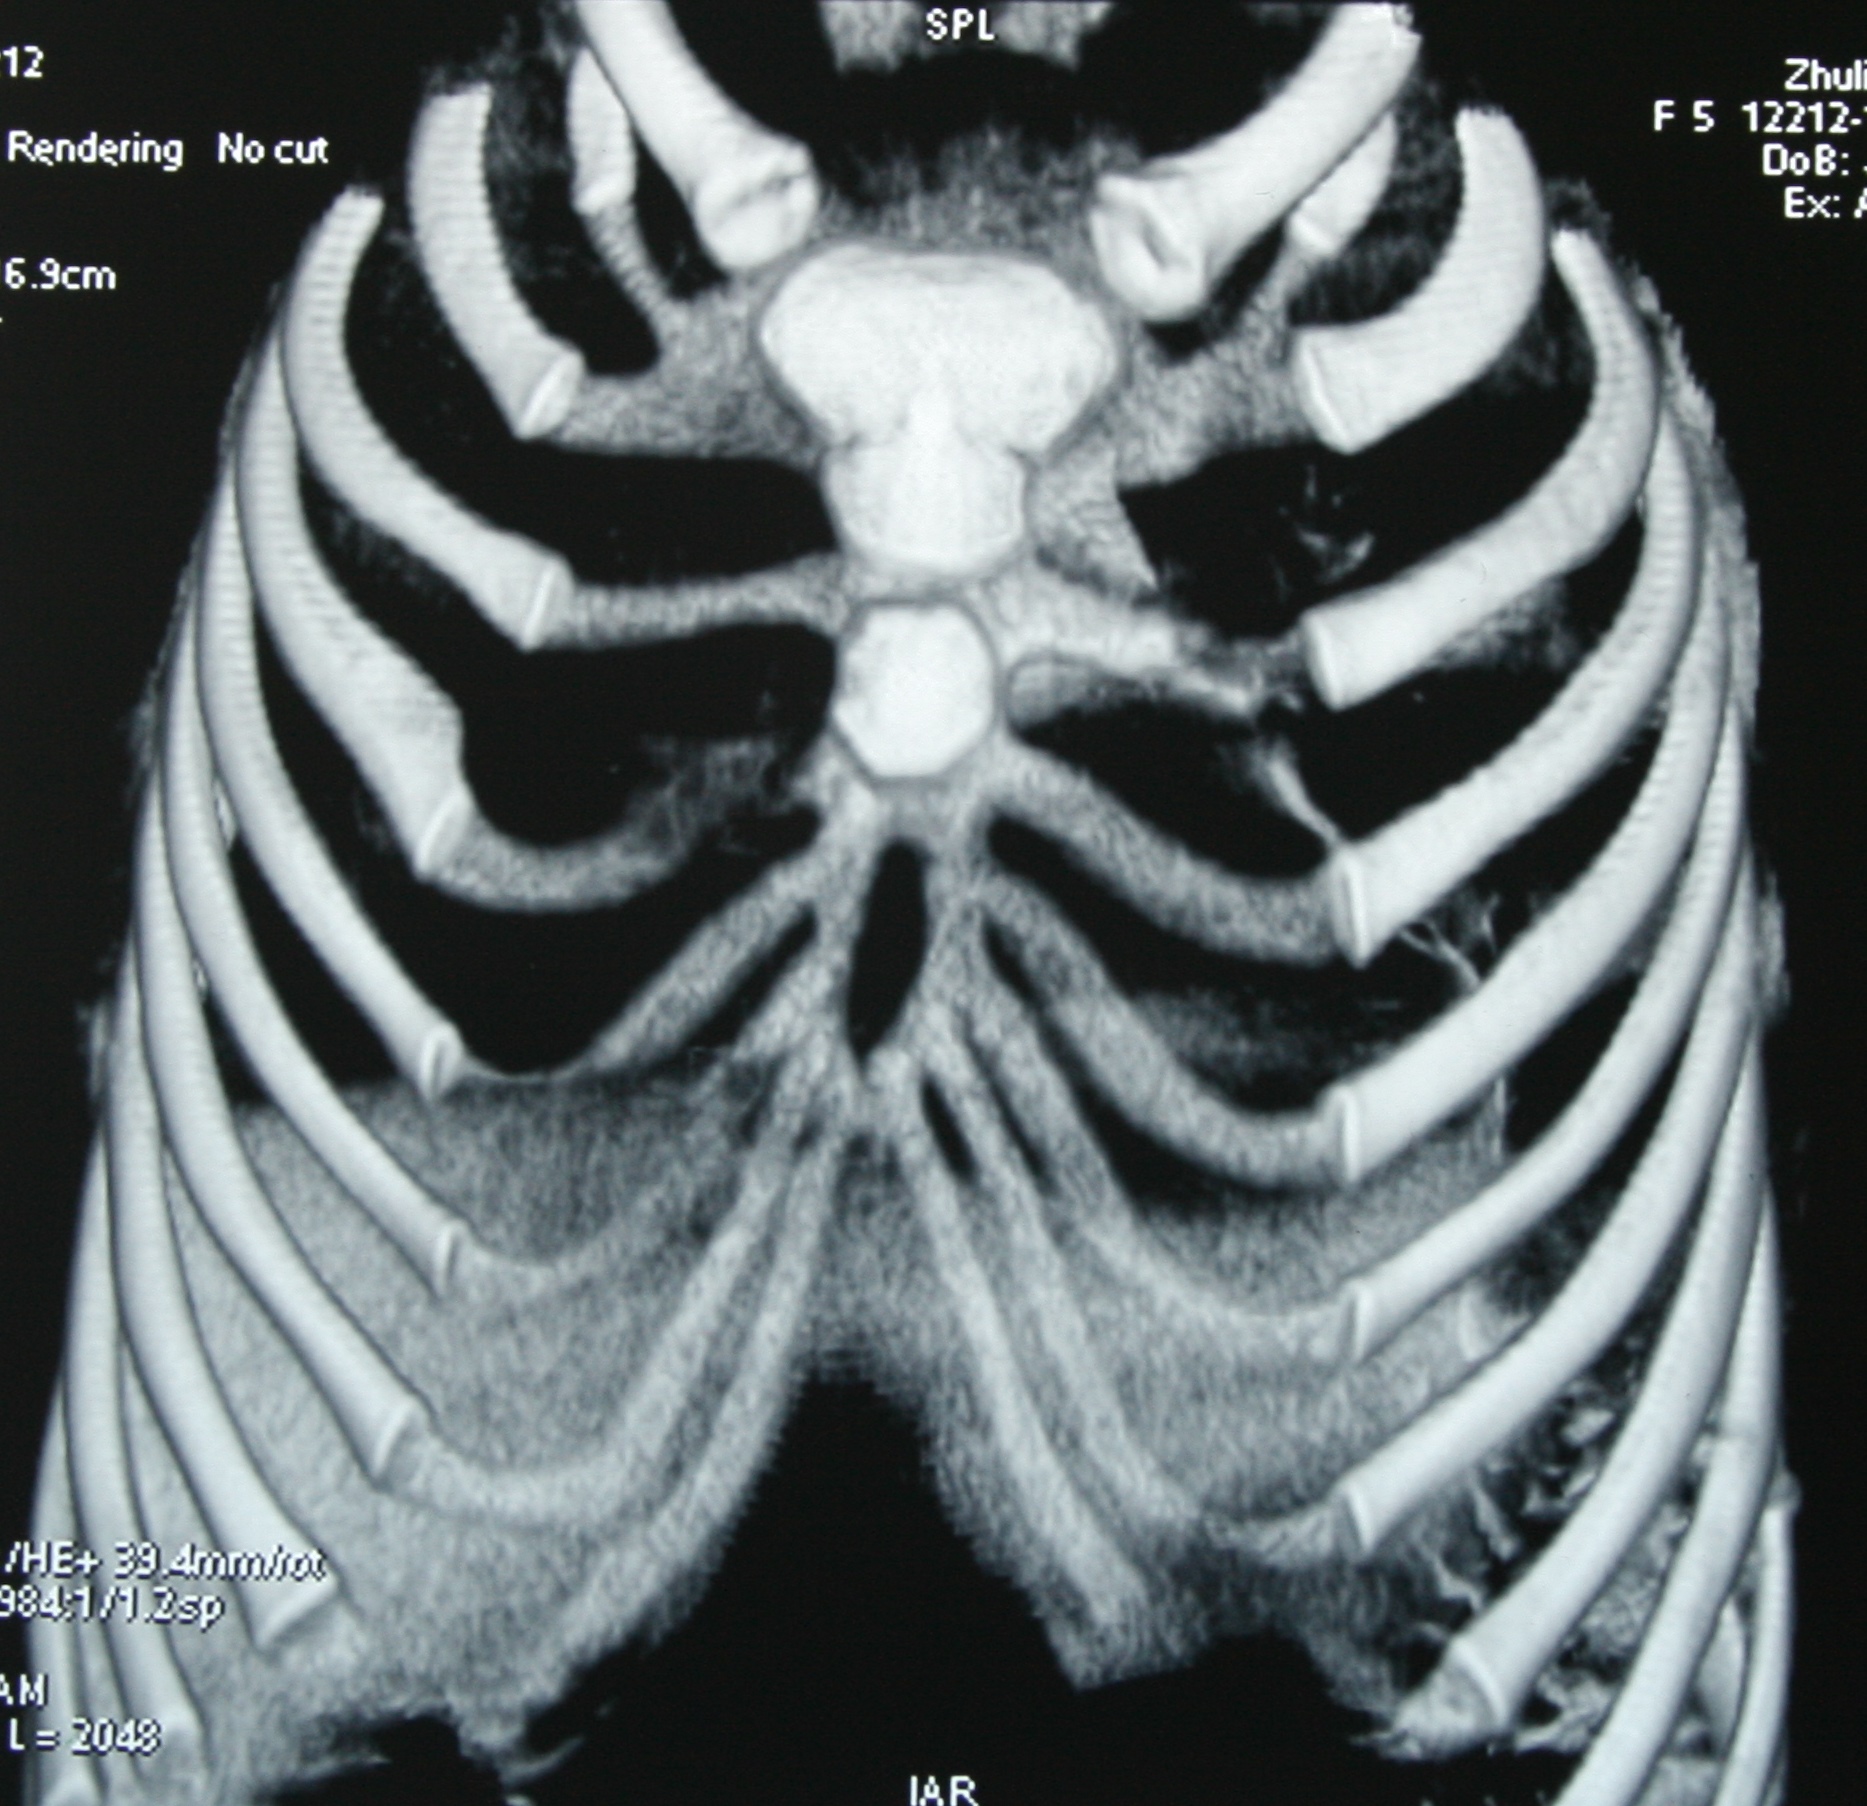

Медицина и диагностика: Аномалии ребер на рентгене